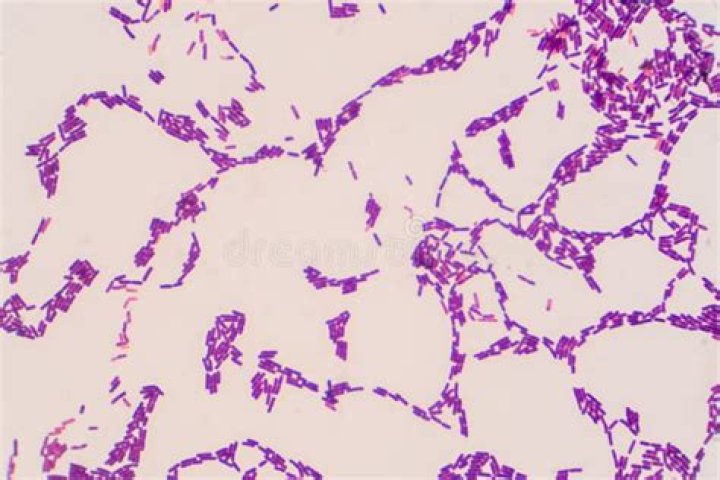

Bacillus anthracis (B. anthracis) is a Gram-positive rod-shaped bacterium that is the causative agent of the disease anthrax. B. anthracis rods typically have dimensions of approximately 1 μm by 4 μm and may occur in chains resembling “boxcars” when observed under a microscope.

Bacillus anthracis — Gram Stain Forms oval, central to subterminal spores that do not swell the bacterial cell.

Bacillus anthracis — Key Characteristics Large, box-car shaped, gram-positive rod in short or long chains. Non-swelling, oval spores formed when grown on culture media. (Not usually seen in clinical specimens.)